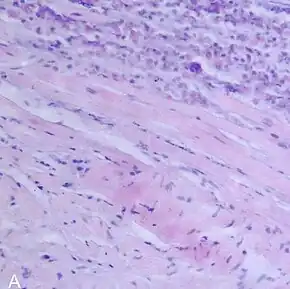

Giant-cell myocarditis, with multinucleated giant cells.